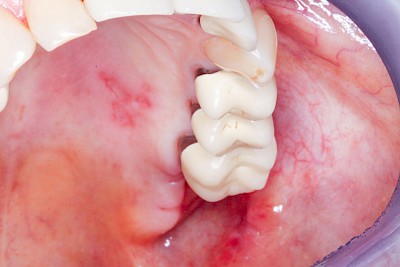

Aphte

Aphten lassen sich gut von Herpes unterscheiden, da Aphten in aller Regel nur einzeln und nicht Gruppiert auftreten. Die Ursachen sind bis heute nicht ganz geklärt. Unter anderem werden Viren aber auch Veranlagung diskutiert. Aphten sind vor allem nur an nicht-verhornten Schleimhautbereichen (Wange, Lippeninnenseite, Mundboden und Rachen) auf. In seltenen Fällen können die Blasen sehr groß sein oder doch in großer Zahl auftreten – hier sind Störungen des Immunsystems (Auto-Immunerkrankungen) häufig die Ursache.

Beispiele26 Bilder